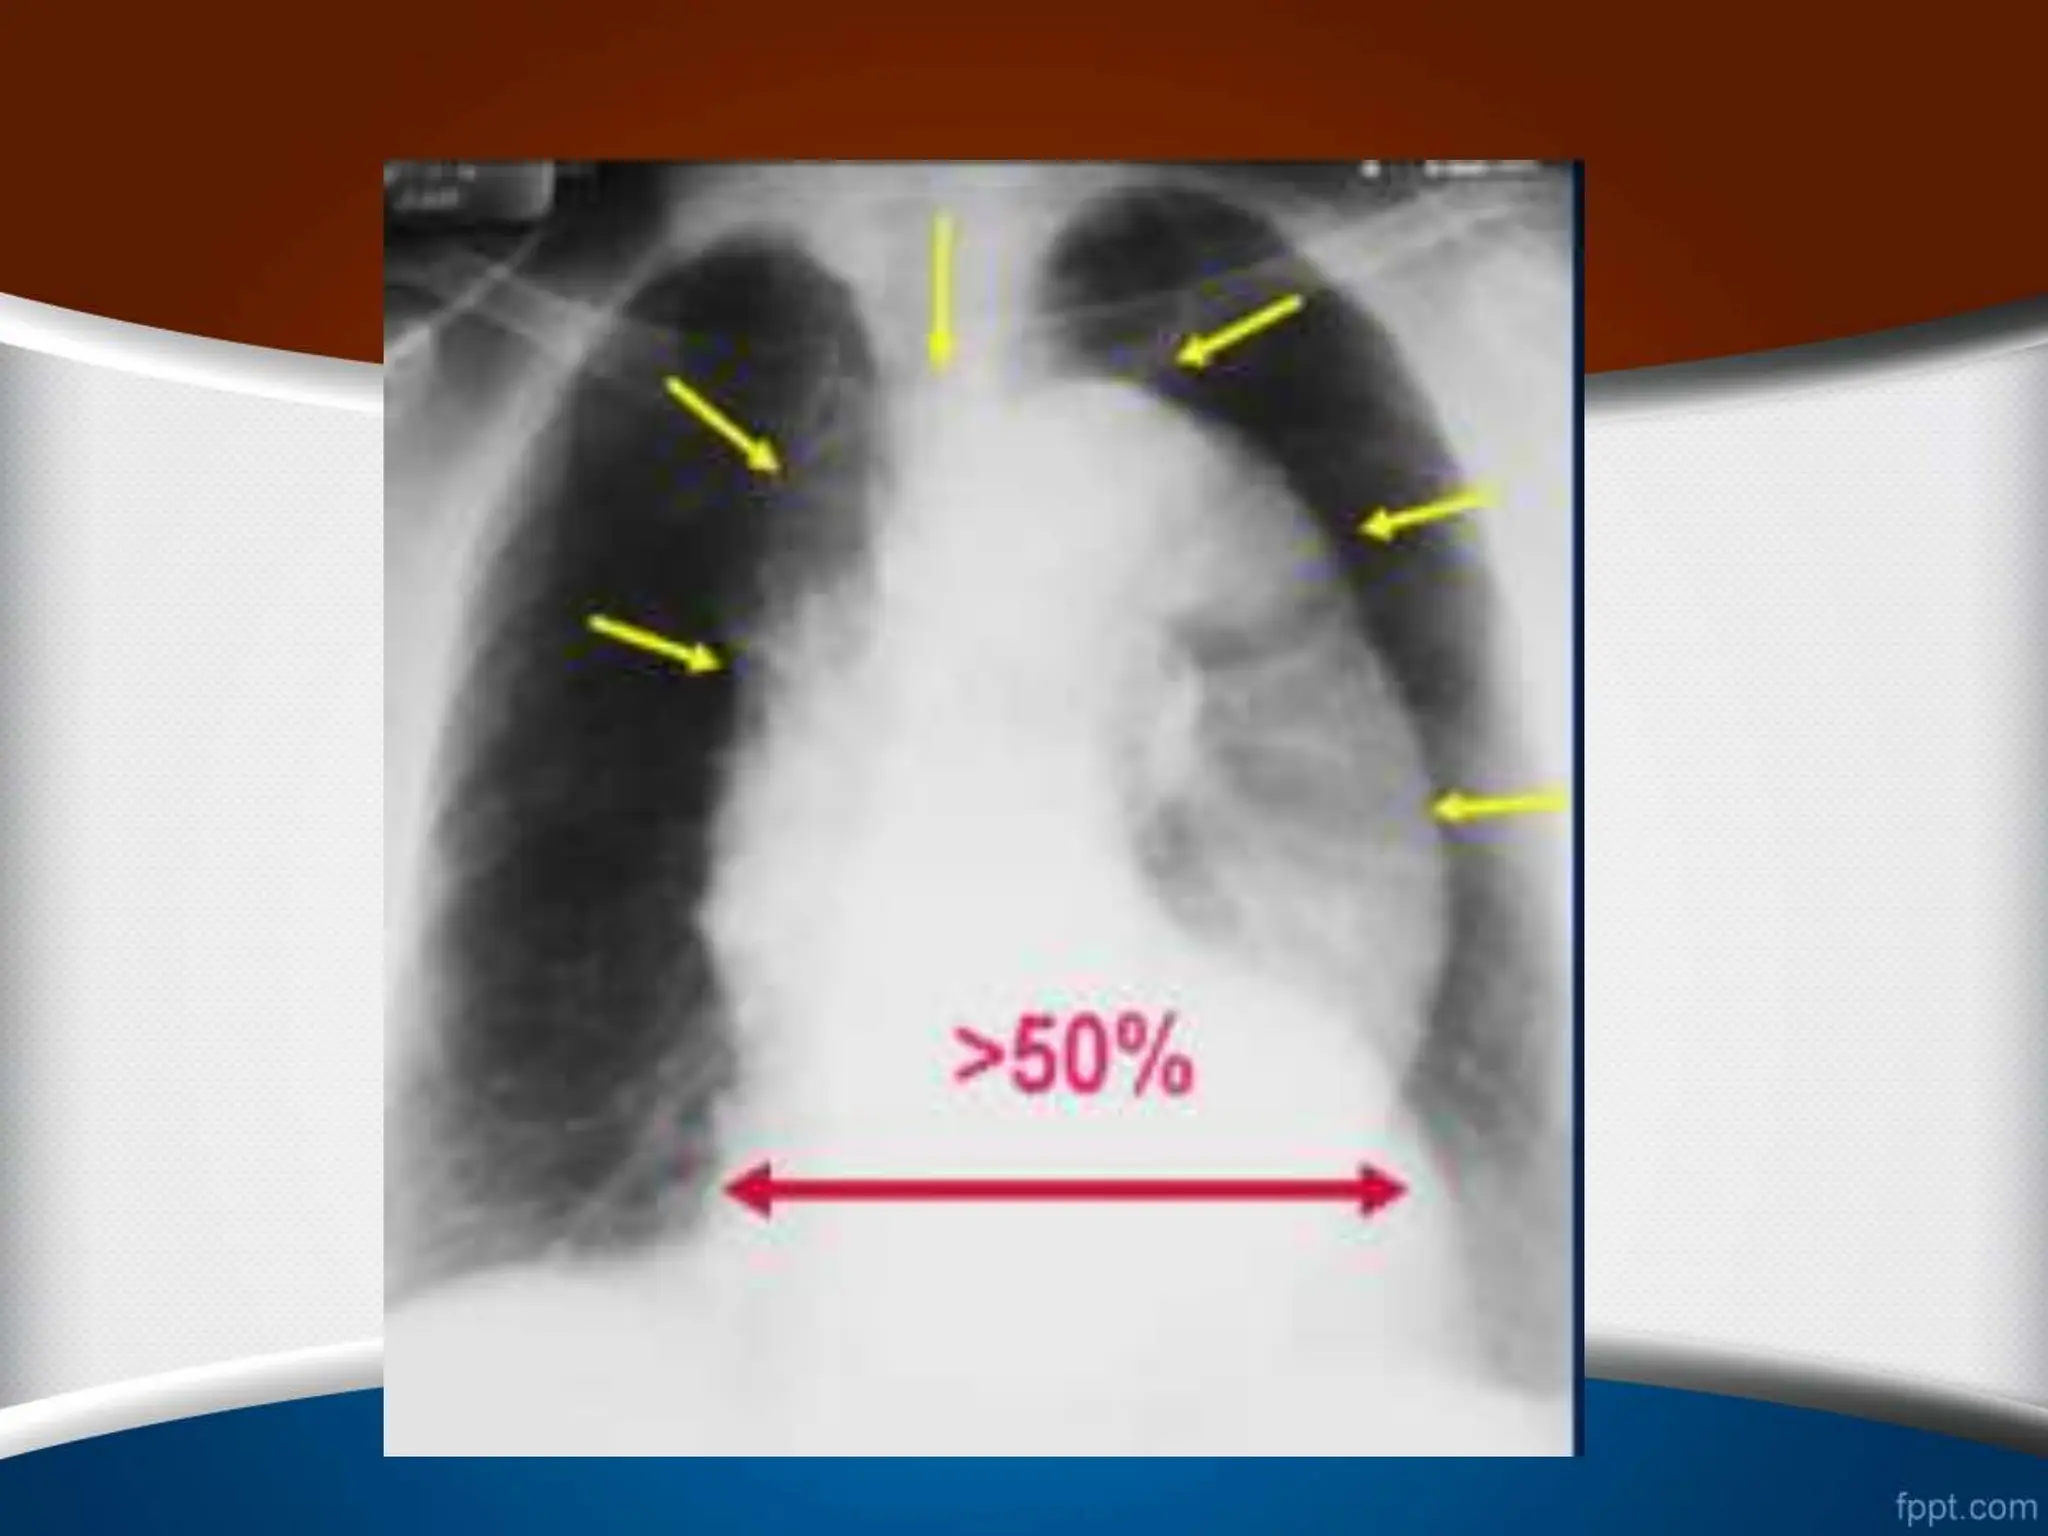

‫قلب‬ ‫ی‬ ‫اندازه‬

•

‫کاردیوتوراسیک‬ ‫نسبت‬ ‫نرمال‬ ‫حالت‬ ‫در‬

(

CTR

)

‫افراد‬ ‫در‬

‫از‬ ‫کمتر‬ ‫بالغ‬

50

%

‫است‬

.

‫این‬ ‫مسن‬ ‫افراد‬ ‫و‬ ‫کودکان‬ ‫در‬

‫نسبت‬

‫تا‬

55

‫باشد‬ ‫می‬ ‫قبول‬ ‫قابل‬ ‫هم‬

‫قلب‬ ‫ی‬ ‫اندازه‬ • ‫کاردیوتوراسیک‬‫نسبت‬ ‫نرمال‬ ‫حالت‬ ‫در‬ ( CTR ) ‫افراد‬ ‫در‬ ‫از‬ ‫کمتر‬ ‫بالغ‬ 50 % ‫است‬ . ‫این‬ ‫مسن‬ ‫افراد‬ ‫و‬ ‫کودکان‬ ‫در‬ ‫نسبت‬ ‫تا‬ 55 % ‫باشد‬ ‫می‬ ‫قبول‬ ‫قابل‬ ‫هم‬ . •